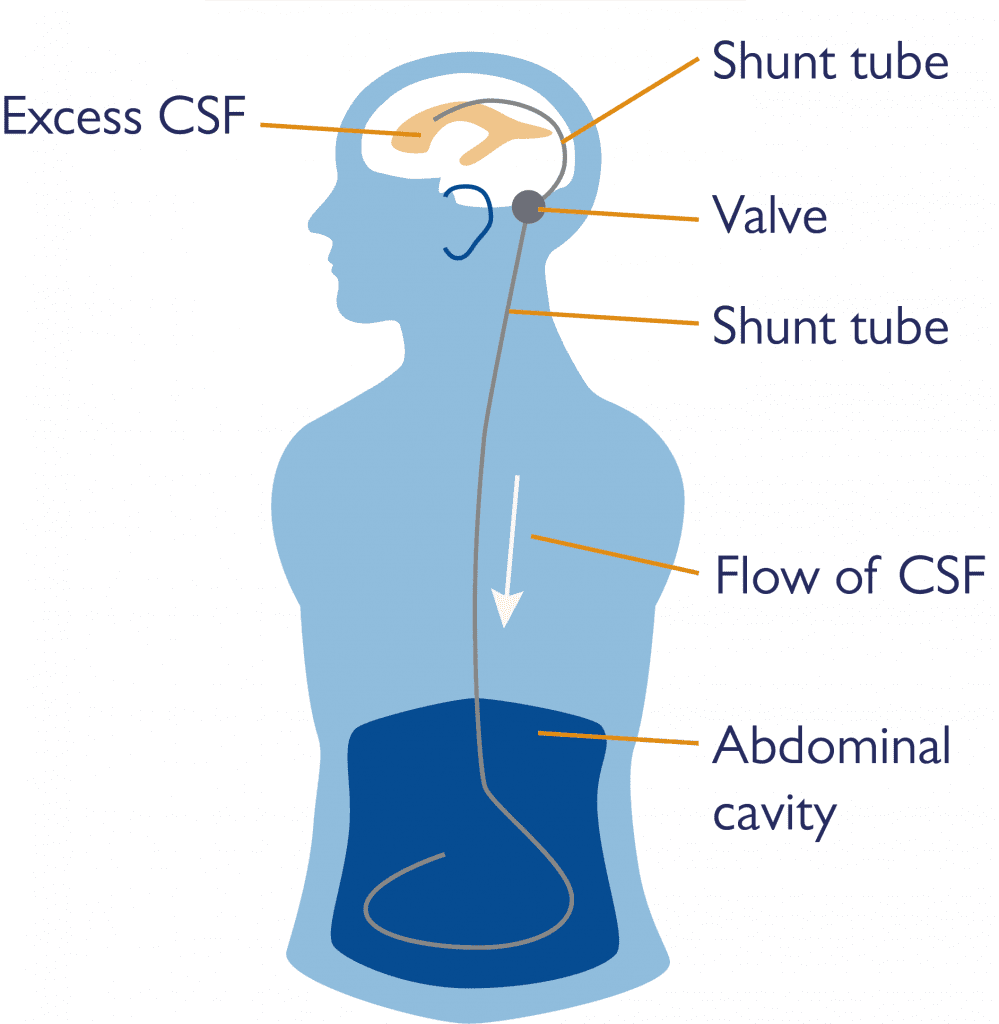

Brain & Spine Foundation | Hydrocephalus and shunts

Shunt Procedure for Hydrocephalus

Hydrocephalus Is Most Often Treated By Surgically Inserting …